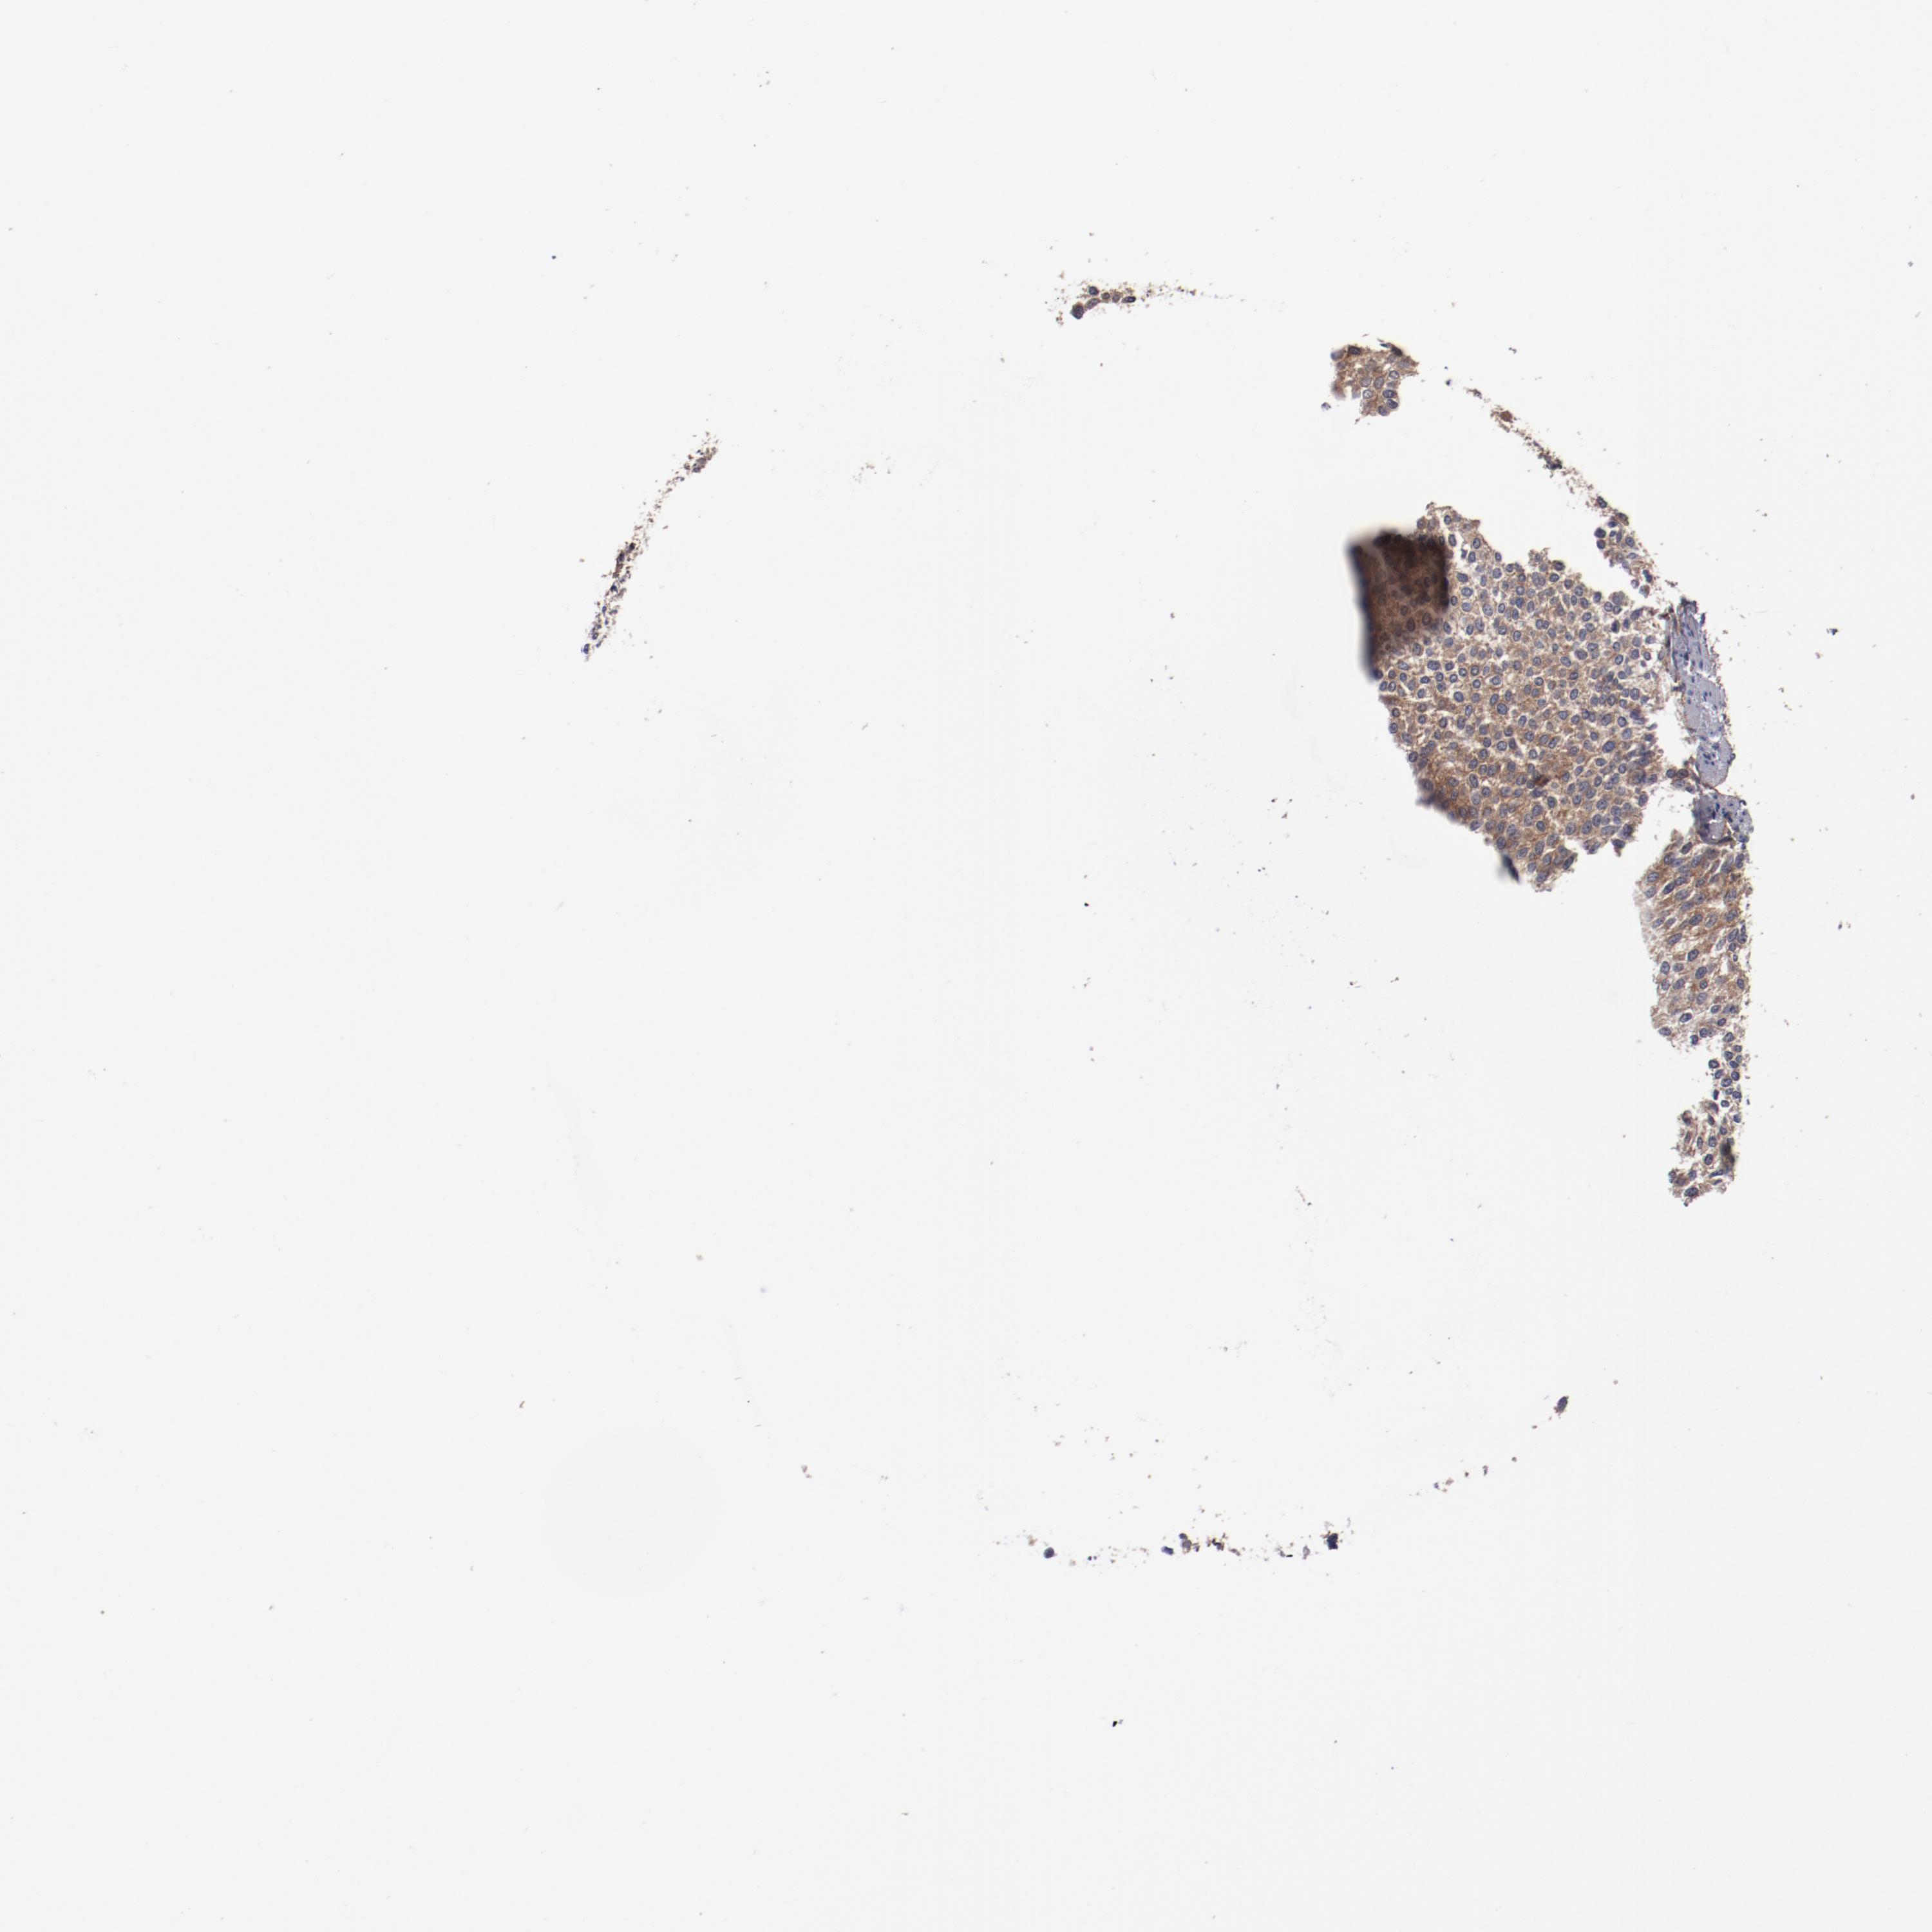

UROTHELIAL CANCER - Protein expressioni

A mouse-over function shows sample information and annotation data. Click on an image to view it in a full screen mode. Samples can be filtered based on level of antibody staining by selecting one or several of the following categories: high, medium, low and not detected. The assay and annotation is described here.

Note that samples used for immunohistochemistry by the Human Protein Atlas do not correspond to samples in the TCGA dataset.

Antibody stainingi

Antibody staining in the annotated cell types in the current human tissue is reported as not detected, low, medium, or high, based on conventional immunohistochemistry profiling in selected tissues. This score is based on the combination of the staining intensity and fraction of stained cells.

Each image is clickable and will lead to virtual microscopy that enables deeper exploration of all samples and also displays staining intensity scores, fraction scores and subcellular localization as well as patient and tissue information for each sample.

Antibody HPA004113

Urothelial carcinoma, Low grade